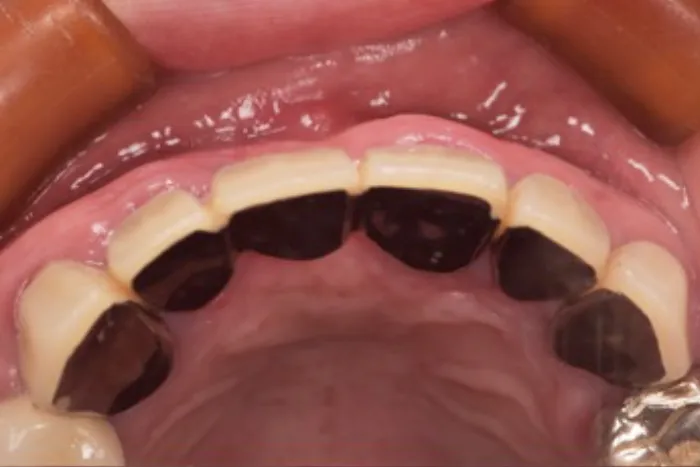

症例② 前歯が一本だけ長いのが気になる

Before

After

| 主訴 | 前歯が一本だけ長いのが気になる |

|---|---|

| 治療期間 | 8ヶ月 |

| 治療費 | 結合組織移植術 77,000円 ※保健治療の金額は含みません |

| 治療内容 | 根管治療・結合組織移植術・レジン前装冠 |

| 治療のリスク | 術後の腫脹・出血 / 歯肉退縮による金属色の露出 |

▲治療のコメント

歯を抜いて歯茎が退縮してしまったことが原因で歯が長くなっていました。なので、上顎口蓋から結合組織を移植することで退縮した歯肉を再建しました。その上でブリッジのやり直しを行いました。